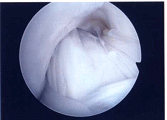

第1段階軟骨形成術

軟骨障害は最初亀裂または剥離で始まります。この状態が第一段階軟骨障害です。このことはあまり一般に知られていません。この最初の亀裂や剥離状態のうちに対処することが最も結果が良好となります。亀裂や剥離が進んでしまうと②の状態になります。

第2段階軟骨形成術

軟骨の剥離や亀裂が①より少し進んだ段階です。放っておくとさらに軟骨欠損が進み軟骨障害は広くなり且つ深くなります。この段階ではまだドリリングなどの操作は不要です。第3段階軟骨障害との間は幅広く関節鏡で見てみないと最終的に判断できません。この段階では手術結果は比較的よく平均75~90点ほどになります。